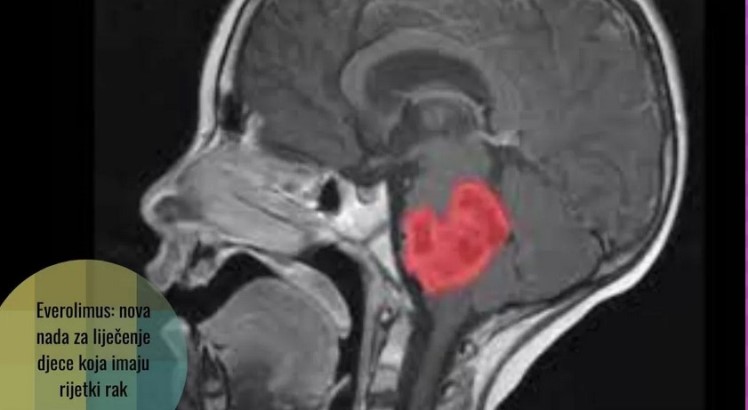

Kada mu je dijagnosticiran gliom moždanog debla, poznat i kao difuzni intrinzični gliom moždanog debla (Diffuse intrinsic pontine glioma – DIPG), Lucas je imao 6 godina i život mu je bio ozbiljno ugrožen. Ljekari su mu davali godinu dana života. Ovaj posebno agresivni tip raka napada djecu, a zbog svoje lokacije u moždanom stablu, hirurško uklanjanje nije opcija. Sve do nedavno, prognoza za djecu s ovim oblikom raka bila je sumorna, s većinom slučajeva koji nisu preživjeli više od godinu dana nakon dijagnoze. Lukas sada ima 13 godina i rak mu se povukao.

Lucasova priča o preživljavanju započela je kada su ga njegovi očajni roditelji odveli u Francusku kako bi bio dio BIOlogical MEdicines for Diffuse Intrinsique Pontine Glioma (DIPG) Eradication (BIOMEDE) studije, koja je istraživala mogućnosti biološke terapije za DIPG. Ova revolucionarna studija je uključivala 233 djece, a Lucas je bio jedan od njih. Rezultati studije su objavljeni u maju 2023. ali tek sad imamo vijest da se kod Lukasa tumor u potpunosti povukao. Ključni korak u ovom istraživanju bio je izdvajanje malenog dijela tumora svakog pacijenta radi detaljne analize molekularnog profila. Na temelju rezultata biopsije, liječnici su odabirali najprikladniji lijek za svakog pacijenta.

Lucas je bio tretiran lijekom everolimusom, a rezultati su bili izvanredni. Nakon sedam godina, Lucas je proslavio svoj 13. rođendan – što je bilo nezamislivo nakon prvobitne prognoze da će mu život trajati samo godinu dana. Everolimus (Afinitor) proizvodi Novartis a inače je lijek koji se koristi kao imunosupresant kod transplantacije organa. Lijek je inhibitor proteina zvanog mTOR kinaza, važnog u diobama stanica i metabolizmu.